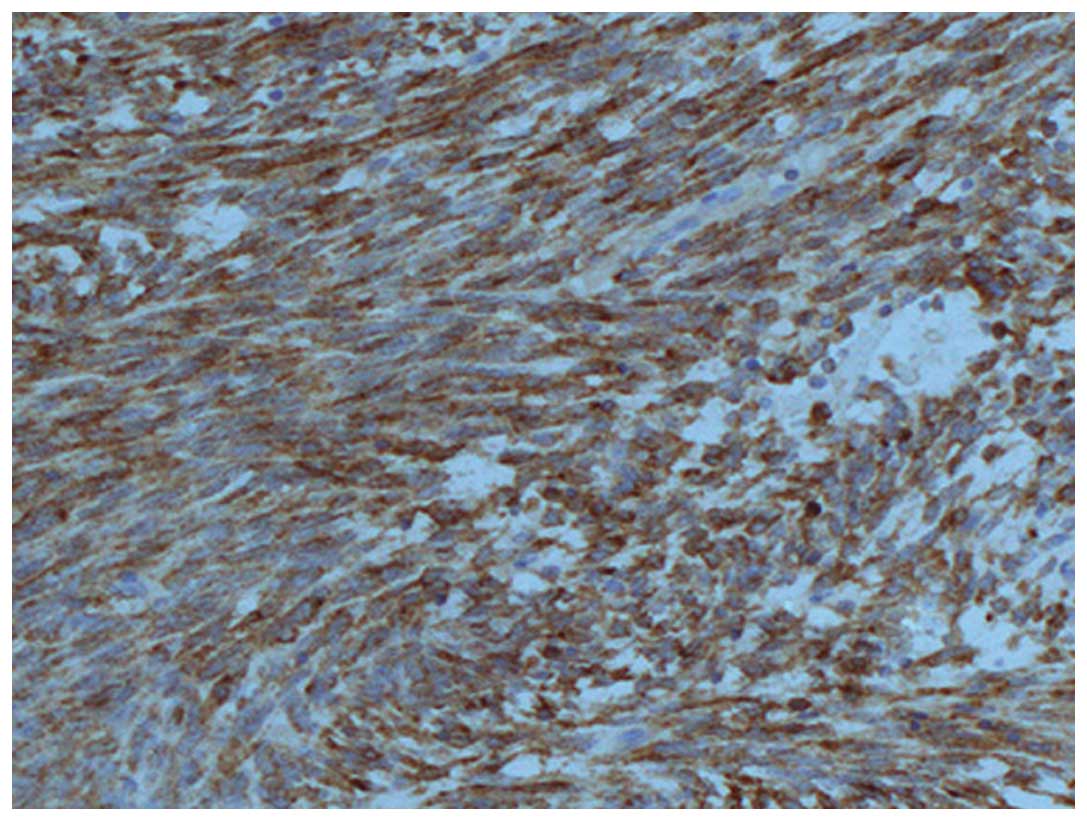

Figure 4.

Immunohistochemistry staining revealed the tumour cells were positive for vimentin (stain, hematoxylin and eosin; magnification, ×200).

Diagnosis of primary pulmonary synovial sarcoma was based on pathological and immunohistochemical analyses, as well as physical and radiological examinations to exclude alternative primary tumors and metastatic sarcoma. Primary pulmonary synovial sarcomas are of four subtypes: Monophasic fibrous (spindle), monophasic epithelial, biphasic and poorly differentiated, among which the former two are most common (12). Immunohistochemical examination may be useful in differentiating synovial cell sarcomas from other sarcomas. In recent studies, synovial cell sarcomas were shown to be almost uniformly positive for vimentin and bcl-2, as well as positive for EMA in 55–91% of cases, cytokeratin in 70%, and CD99 in 90% (13,14). In the present case study, histological results revealed that the neoplastic cells were of moderate size with obvious nucleoli and thick cell membranes, as well as with varying arrangements of epithelial cells and spindle cells. The following immunohistochemical analysis revealed that the tumor cells were positive for EMA, bcl-2, CD99 and vimentin, but negative for S-100, SyN, Myo-D1 and CD20. On the basis of these results, primary pulmonary synovial sarcoma was diagnosed. Cytogenetic testing may be performed when diagnosis is unclear, which is a new diagnostic method for synovial sarcoma (15). The t (X;18) (p11.2;q11.2) translocation, commonly identified in synovial sarcoma, results from the fusion of the SYT gene on chromosome 18 to either of two closely related genes, SSX1 and SSX2, on chromosome X.